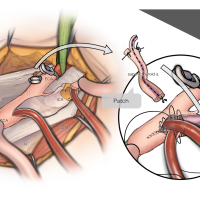

術後イラストシリーズ

脳神経外科速報2023vol.33(メディカ出版)寄稿シリーズ